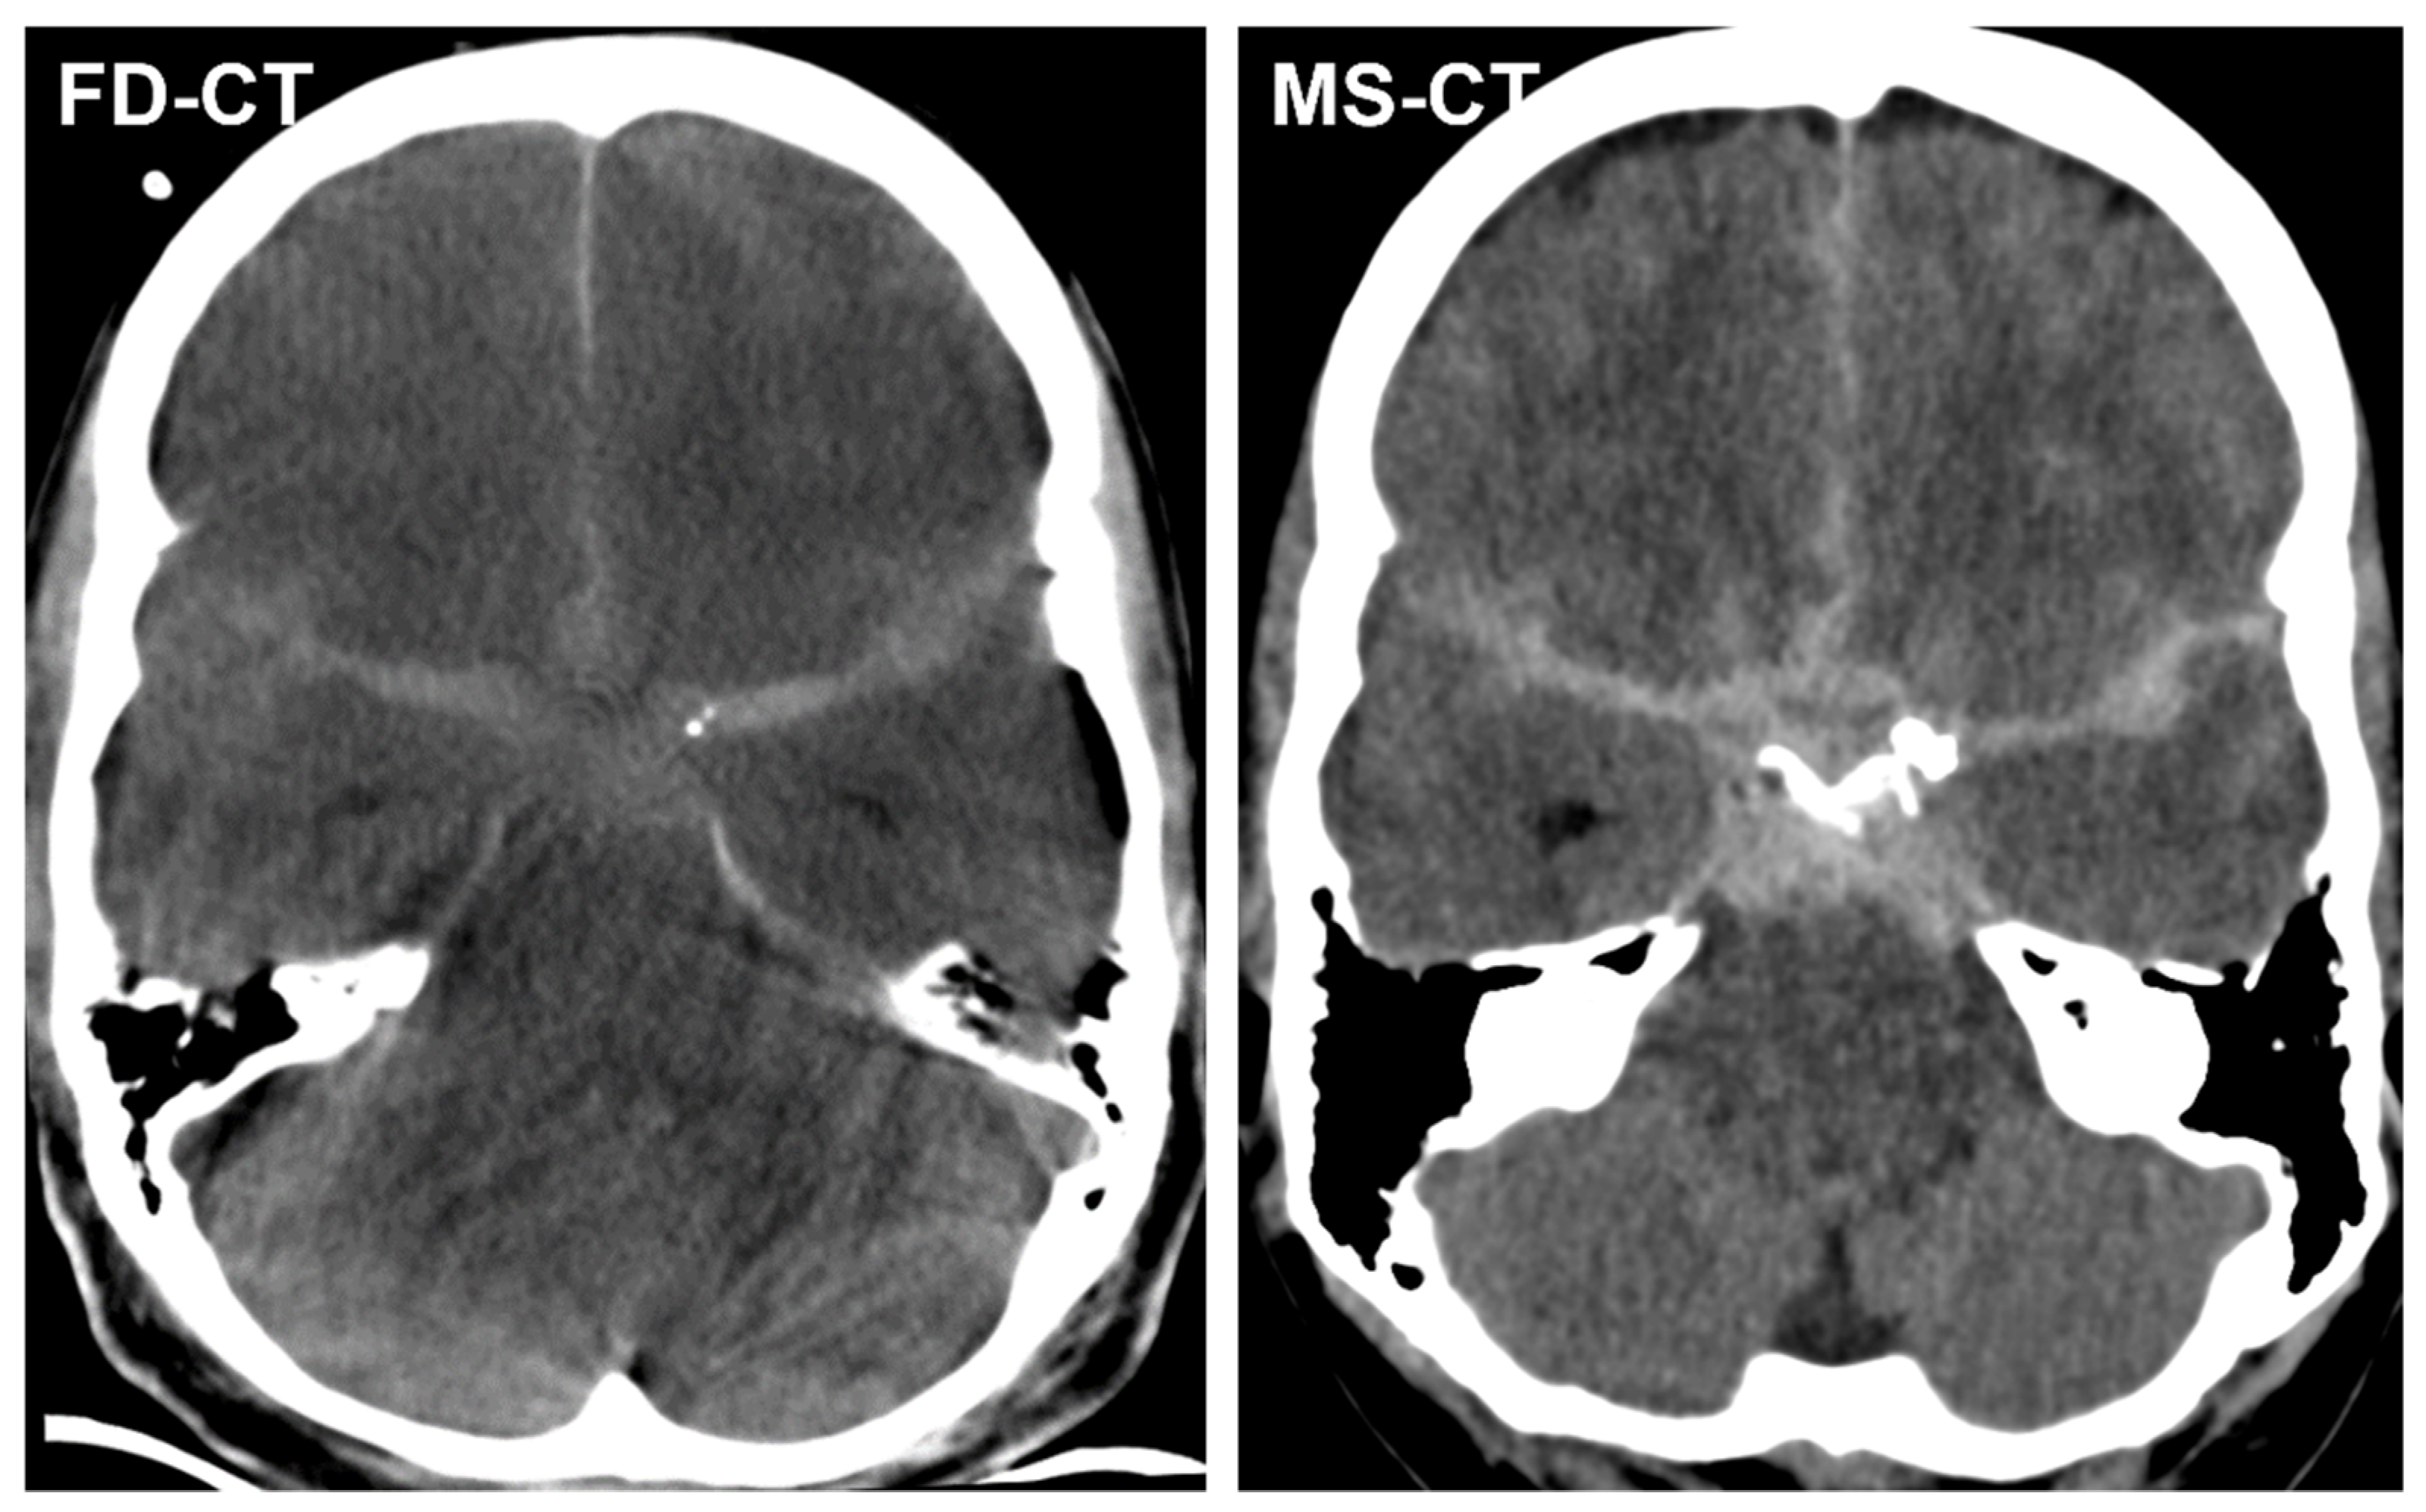

3.3.1. Blood Distribution

3.3.2. External Ventricular Drain Position

3.3.3. Acute Obstructive Hydrocephalus

3.4. Quantitative Analysis